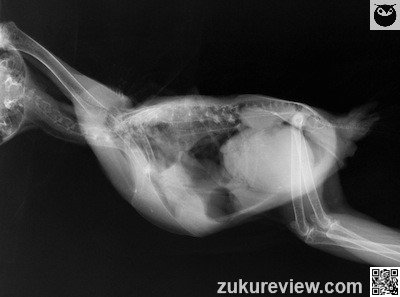

A long eared owl with a history of wing amputation is presented with anorexia, lethargy, and ataxia. Radiograph are shown below.

The top image is a plain lateral radiograph. The bottom lateral radiograph was obtained after oral administration of 7 mL 50% barium suspension.